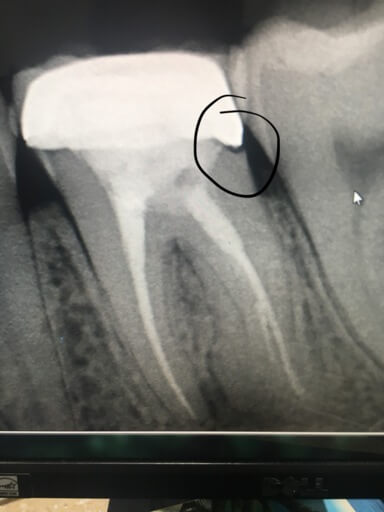

It appears in the radiograph you submitted that the distal margin of the crown is open. The crown could have fit improperly when it was cemented in, or decay may have formed since it was placed. It is hard to say if there is active decay under the crown, because there is metal in the crown, which appears opaque on the radiograph. The only way to determine if there is decay and the extent, is to remove the crown and have a new crown fabricated. If your obgyn approves for you to have treatment, it is a very predictable procedure with minimal risk involved. If your doctor does not give you permission for treatment at this time, there is a risk that a cavity could continue to grow under the crown and affect the nerve tissue. It is always better to restore the tooth as soon as you find an issue, it will only continue to get worse. As far as a night guard, it is a great option for reducing damage to tooth structure during clenching and grinding. An impression is taken and the appliance fabricated. No anesthetic is involved, so the procedure is completely safe for pregnant and nursing women.